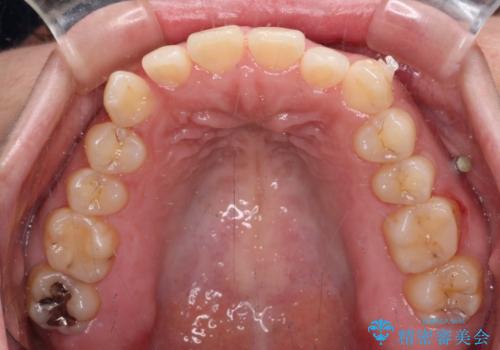

【モニター】カリエール・ディスタライザーを併用した八重歯のインビザライン矯正

- 前歯の叢生と八重歯を気にして来院された患者様です。

目立たない装置を希望とのことで、インビザラインにて矯正治療を行うこととしました。

インビザライン単体で改善することも可能ですが、八重歯とその後方にある歯列を確実移動させないと、上下正中がずれてしまう可能性があります。

インビザライン単体での治療ではなく、カリエール・ディスタライザーという補助装置を併用して、より確実性を上げることとしました。

補助装置で八重歯を解消しながら、並行してインビザラインで歯列を整えることとしました。

カリエールディスタライザーを併用したことで、すっきりとした口元になり、上下の正中を合わせることができました。